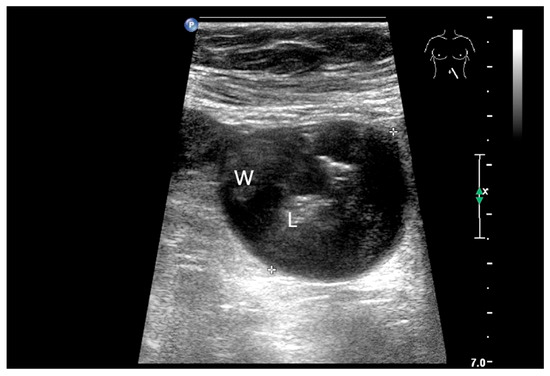

Figure 11.

GIST. A 30 mm large, very hypoechoic, almost anechoic round mass is visible in the left upper abdomen. This is located in the jejunum; the wall (W) and lumen (L) are visible (a). Macro vessels can be distinguished on Power Doppler, demonstrating that the lesion is solid and not cystic (b). On CEUS with 2.4 mL SonoVue (linear transducer 9 MHz), a small wheel-spoke-like vascular branching is visible at the margin (arrow) (c) with centrifugal enhancement (arrow) (d). Hyperenhancement is heterogeneous in the early arterial phase (e,f) and becomes homogeneous in the later course of the arterial phase (g). The extent of the heterogeneously enhanced tumor is marked with arrows (e). The intensity of the enhancement decreases during the first minute. The tumor is marked with arrows (h). Jejunal segment resection revealed the histology of an epithelioid GIST.

Precise descriptions of subepithelial intramural masses including GIST are known from endoscopic ultrasound (EUS) [128]. Despite the lower resolution and proximity, the findings known from EUS can generally be transferred to US. However, in the small intestine, it is much more difficult to classify the layers, as the healthy wall is only up to 2 mm thick. GIST can develop into the lumen of the gastrointestinal tract or be located extraluminally. On EUS as well as on US, small GIST are generally round, homogeneous, and hypoechoic compared to submucosal layer, but isoechoic to the Lamina muscularis propria. On CDI, they show macrovessels. Larger GIST may be lobulated and heterogeneous, show necroses as hypoechoic or nonechoic liquid areas as well as calcifications. Air inclusions in the tumor are an indication of deep ulceration of the tumor surface with central necrosis and connection to the gastrointestinal tract lumen [55] (Figure 11 and Figure 12).